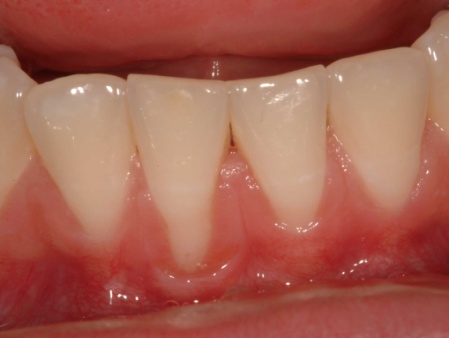

Lower incisor tooth with recession. A gum graft was used to repair this recession.